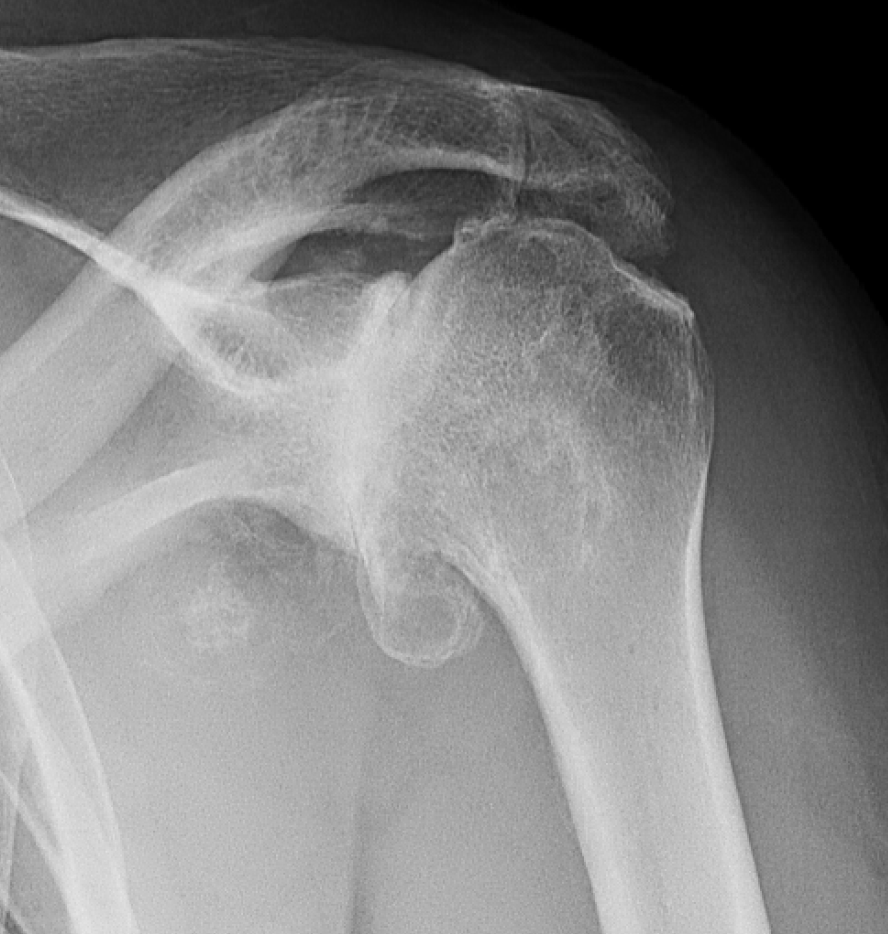

X-ray image of a shoulder showing severe osteoarthritis

• X-rays, which typically show joint space narrowing, bone spurs, and other arthritic changes

X-ray image of a shoulder showing severe degenerative joint diseases